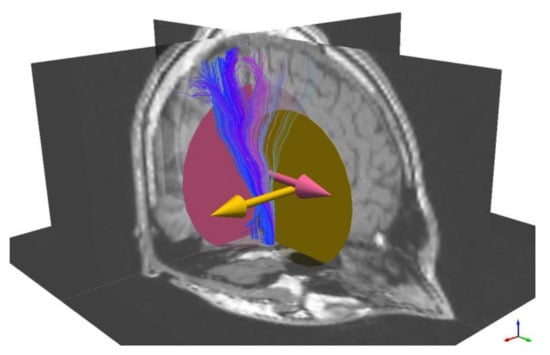

3.1. The Corticospinal Tract

3.2. The Optic Radiation